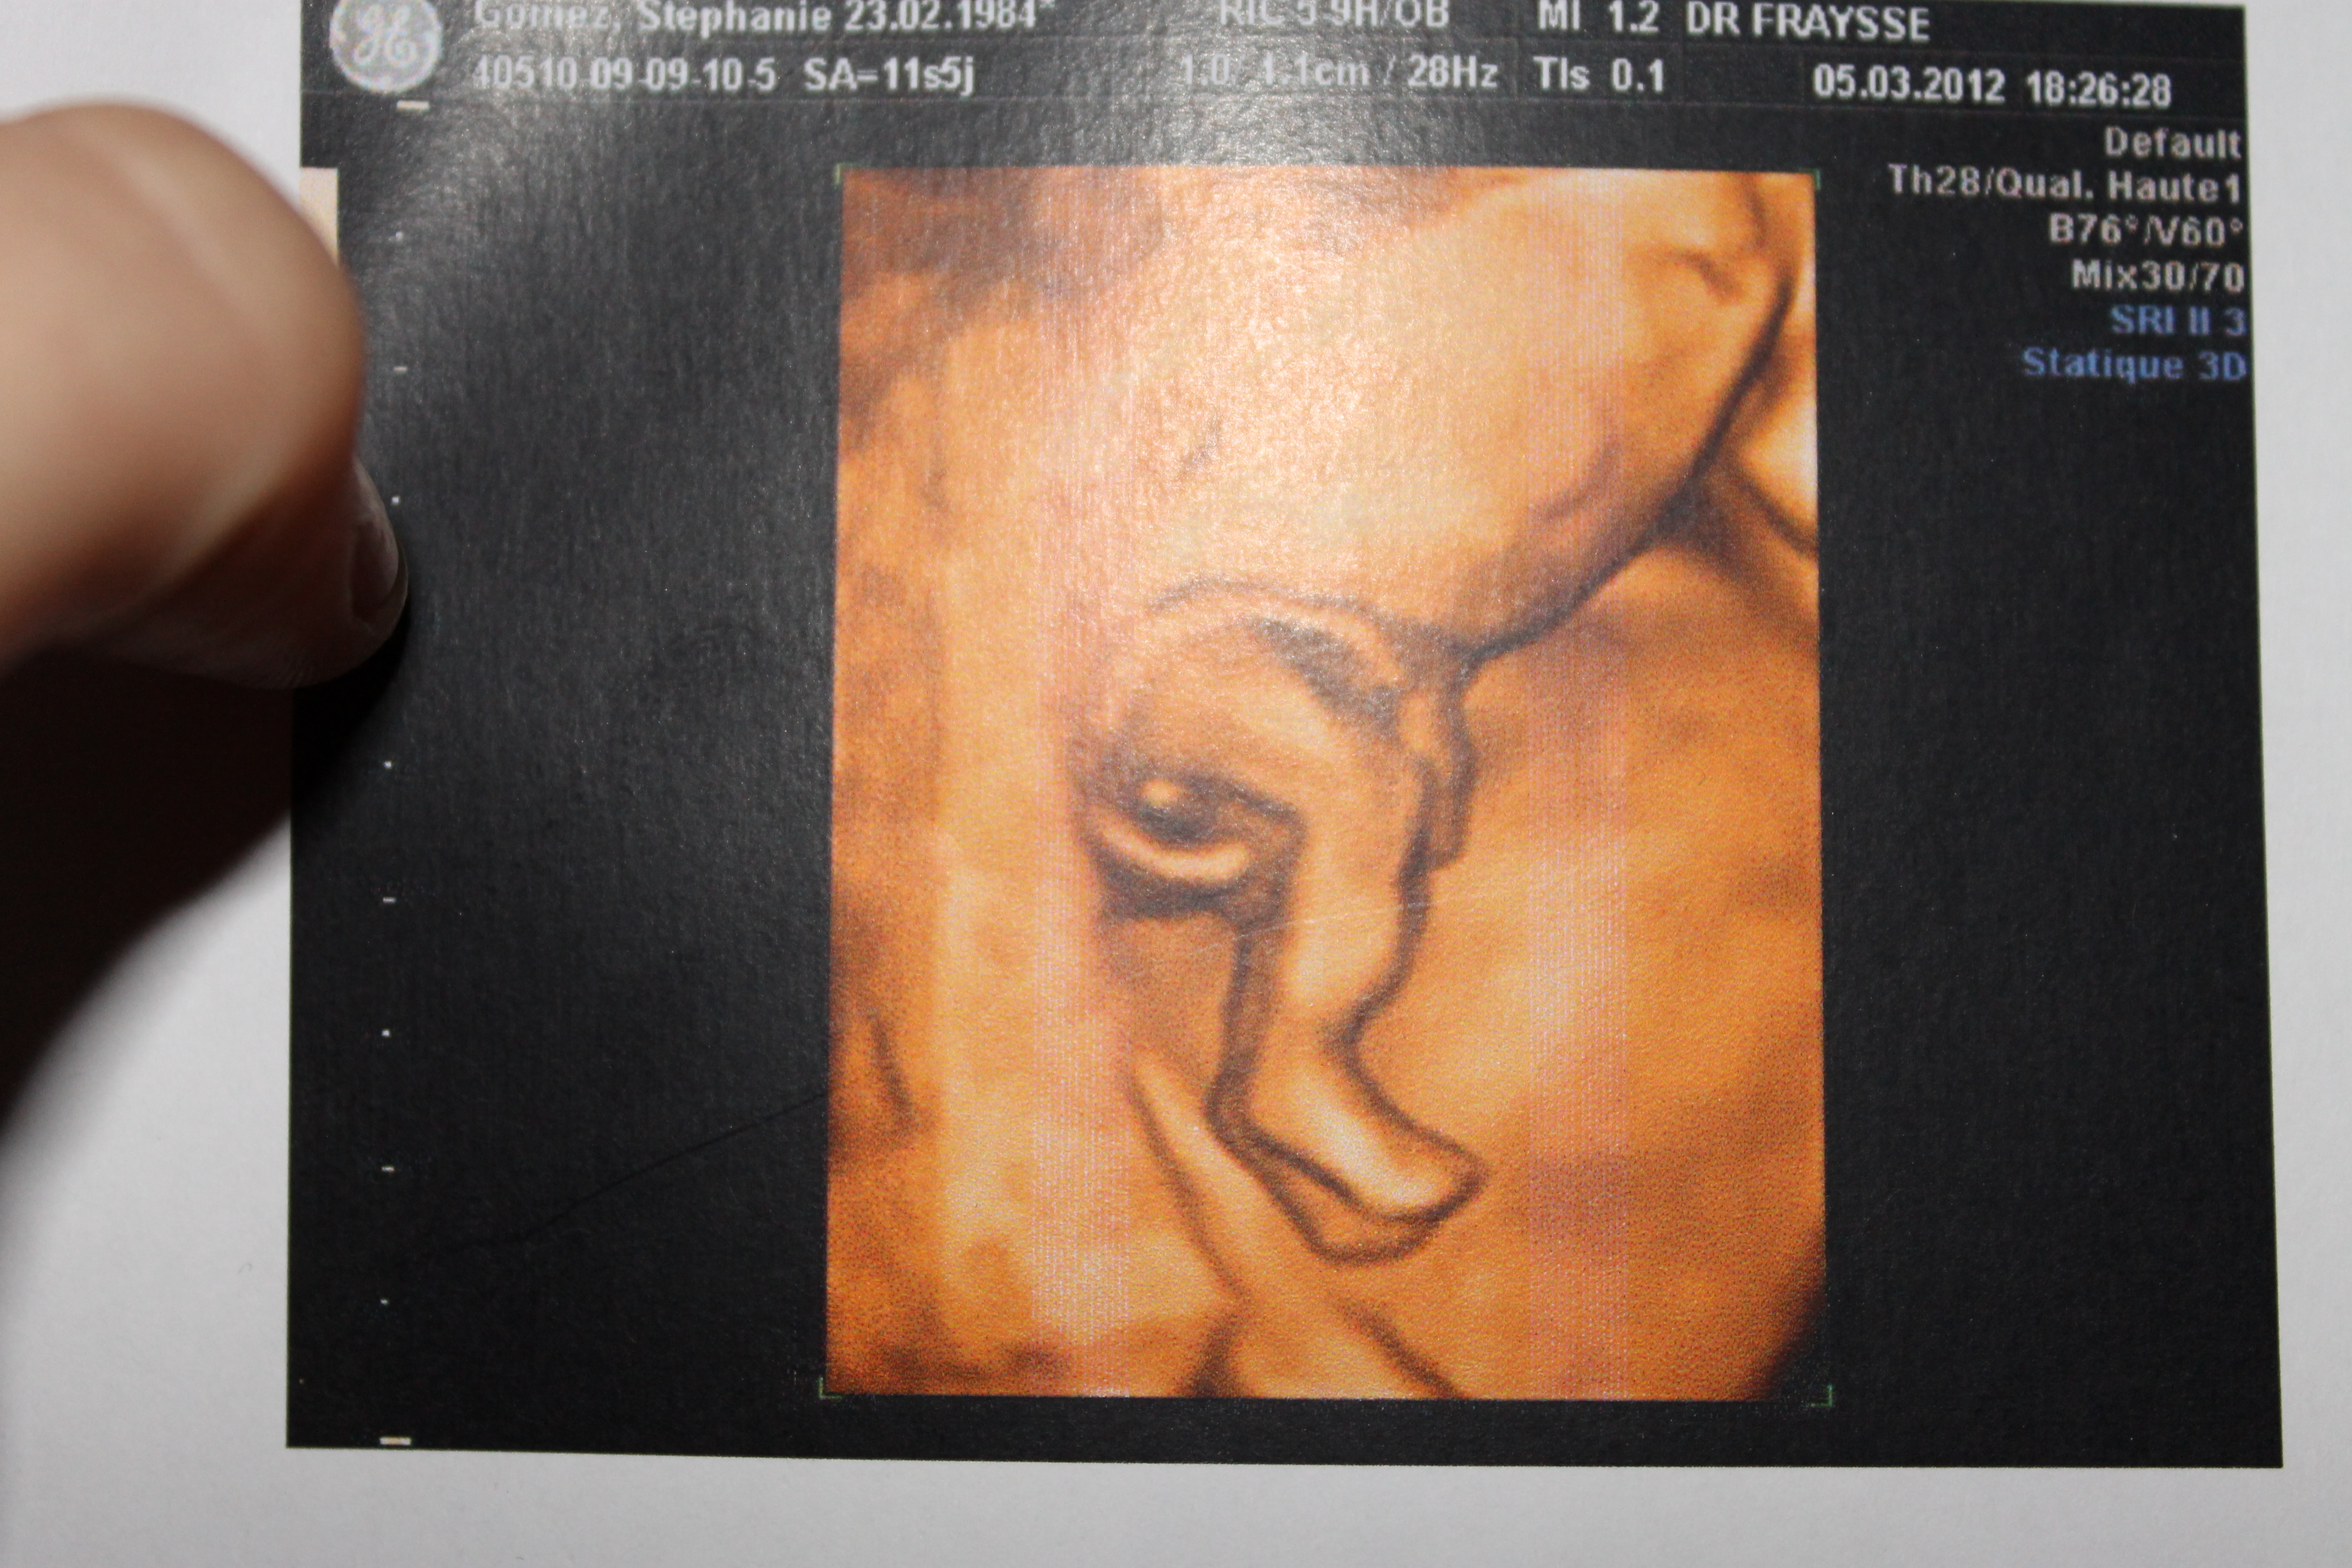

A 19 semaines de grossesse, votre futur bébé continue doucement sa croissance Retour en images sur sa jolie évolution avec une échographie de future maman · 17 semaines de grossesse ou 19 SA votre corps, enceinte Symptômes En raison du bouleversement hormonal (qui a des répercussions sur les ligaments et les articulations) et de Taille du ventre Vous ne pouvez plus cacher votre grossesse, votre ventre est désormais bien rond Bébé poursuit saSemaine 19 les changements chez maman Cette semaine marque la 2ème rencontre avec votre bébé En effet, c'est au cours du 5ème mois, plus précisément entre la 21ème et la 23ème semaine d'absence de règles, que le gynécologue réalise la 2ème échographie dite morphologique

♡♡♡♡ TOUTES LES INFORMATIONS ICI ♡♡♡♡ On se retrouve dans une nouvelle vidéo dans laquelle je vous parle de l'évolution de ma grossesse Dans cette vidéo) Enterprise Get your team aligned with all the tools you need on one secure, reliable video platformEn cette 19ème semaine de grossesse (21 SA), le bébé mesure 21 cm et pèse 335 g Sa tête fait environ 5,5 cm de diamètre

· Où en est Bébé à la 19 ème semaine de grossesse 21 SA ?1108 · Calendrier de grossesse la 19e semaine de grossesse (21e SA) A ce stade, votre bébé mesure 2122 cm environ (de la tête aux talons) et pèse environ 335 g Ses muscles, ses os, ses nerfs se développent, ainsi que son système immunitaire Il bouge de plus en plus Côté bébé un vrai mélomane · 16 / 38 Semaine 17 de grossesse (19 SA) un poivron A ce stade, votre bébé mesure 19 cm de la tête aux talons de grossesse (1213 cm de la tête au coccyx) et pèse environ 0 g Le méconium se forme dans ses intestins Votre 17e semaine de grossesse